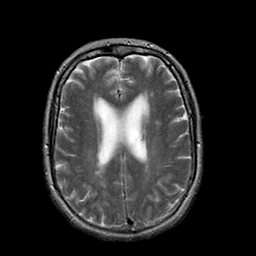

Stroke:T2-weighted MR #1 -- Slice #16

[Home][Help][Clinical] Slice 16